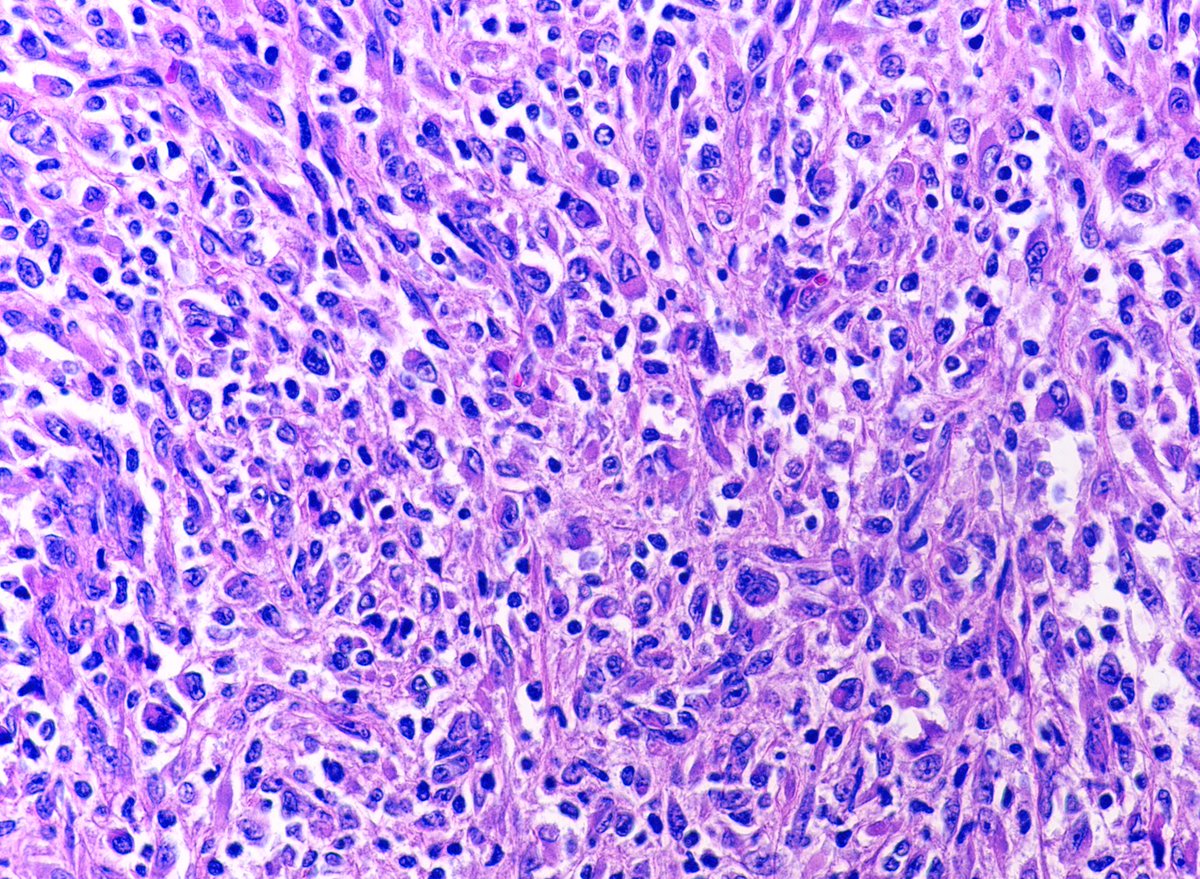

Inflammatory rhabdomyoblastic tumor, initially thought to be a smooth muscle neoplasm in part because myogenin expression is limited - PAX7 is typically diffuse #BSTPath

4

64

162